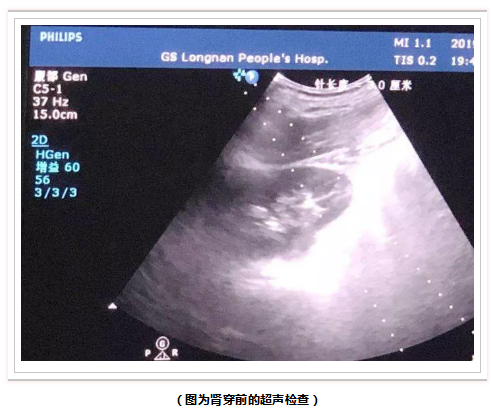

6月20日晚,在青岛市市立医院内科教授张扬、我院肾病科主任刘永峰和功能科主任李荐德的精心准备和协作配合下,共同完成了我市首例超声引导下肾活检穿刺术,填补了我市肾脏病理穿刺的空白。意味着患者以后在我院就可以进行肾穿刺活检术,是我院肾病科诊疗技术的一个重要突破。

三天前肾病科收住一中年男性患者黑某,以下肢浮肿2月余收住入院,入院后完善相关检查,生化检查提示:大量蛋白尿(24h尿量>6g)、高脂血症、高度浮肿和低蛋白血症(血清白蛋白<19g/L),患者表现为典型的肾病综合征,排除了乙肝、狼疮、糖尿病等继发性肾病综合征的可能,肾脏超声检查提示双侧肾脏大小正常,该患者没有肾穿的禁忌症。经副教授张扬及全科医师讨论后决定为其行肾活检穿刺以明确病理诊断,从而指导治疗和判断预后。穿刺过程顺利,取得了满意的肾组织进行送检。

(图为肾病科主任刘永峰行肾活检穿刺)